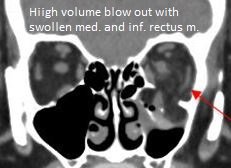

High volume medial orbital wall fracture with possible significant entrapment of the medial rectus muscle and comminuted and minimally depressed nasal bone fractures

Notify emergency room acutely about possible medial rectus entrapment

Urgent (Action Necessary in a few hours)